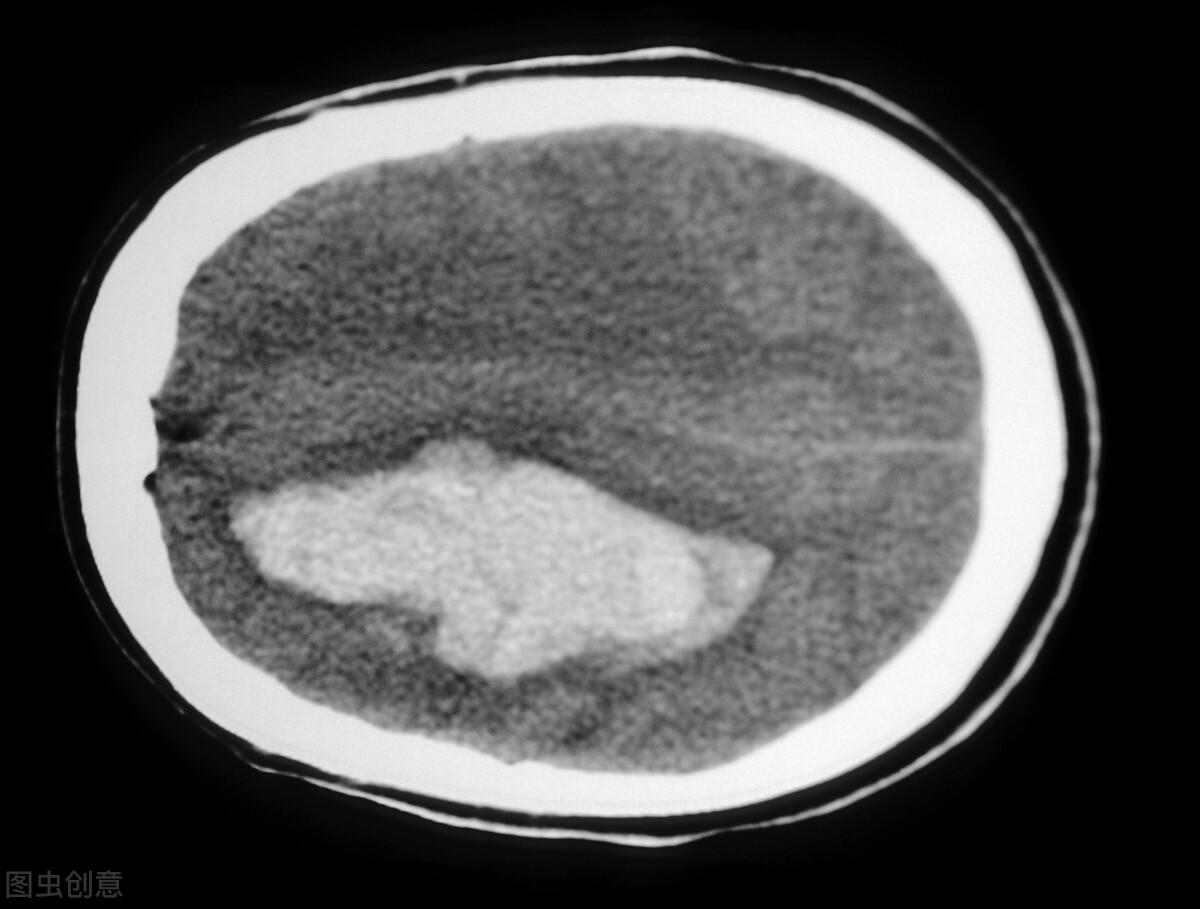

“肺结节”本身不是一种病,只是影像学上的一种概念,即影像学上直径大于或等于3厘米的类圆形或不规则病灶,即可单发也可多发,边界清晰也可不清晰。在通俗点来说就是肺里长了个东西,这个东西直径小于3厘米我们就称之为结节;小于1厘米我们称之为小结节;而直径小于5毫米的话就是微小结节了,所以总结来说肺结节就是一种肉芽类疾病。